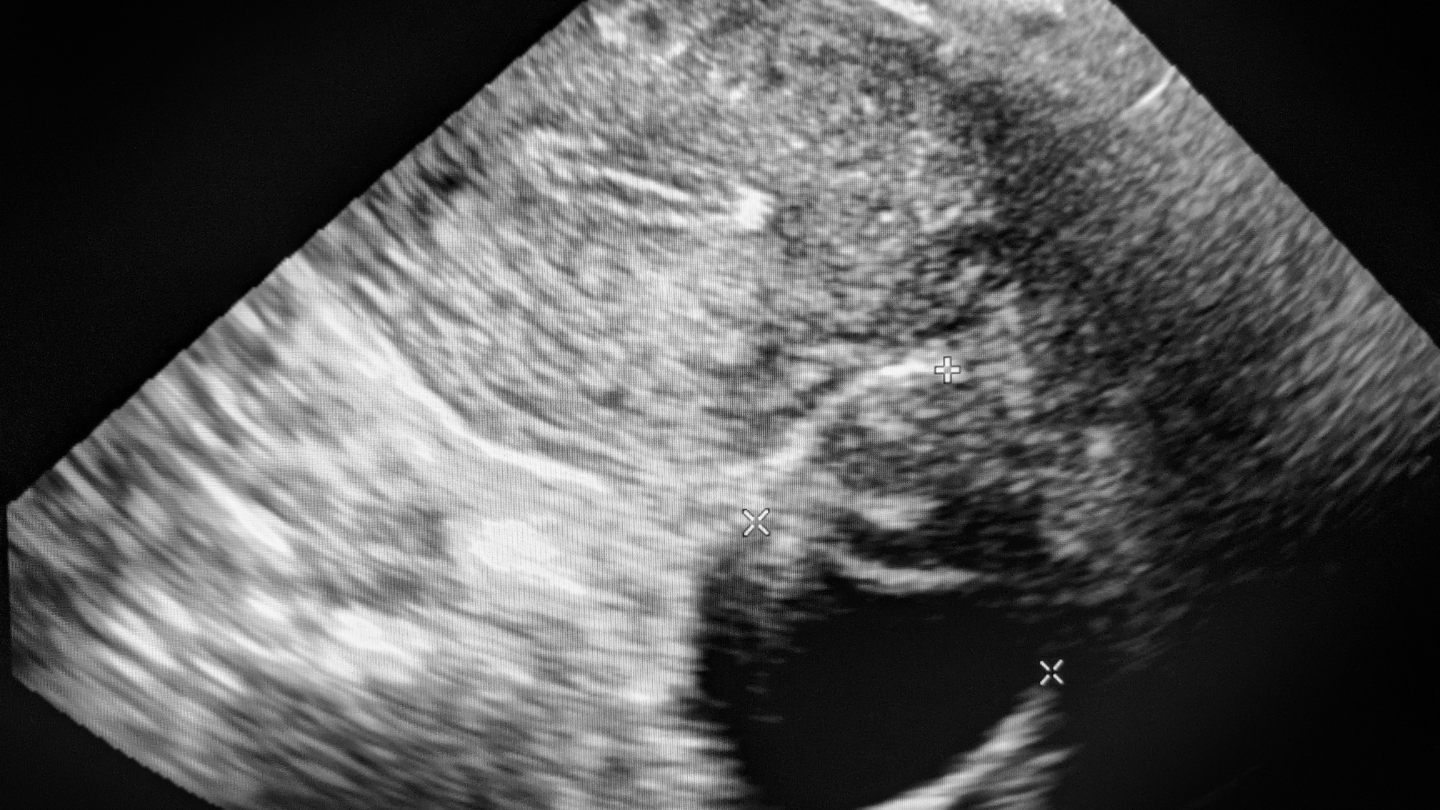

Siêu âm tử cung là phương pháp chẩn đoán hình ảnh phổ biến trong khám phụ khoa và theo dõi thai kỳ sớm. Tuy nhiên, nhiều phụ nữ cảm thấy khó hiểu khi cầm trên tay phiếu kết quả với hàng loạt thuật ngữ chuyên môn. Bài viết này sẽ giúp bạn hiểu rõ cách đọc phiếu kết quả siêu âm tử cung một cách khoa học, dễ áp dụng và phù hợp với thực hành y tế tại Việt Nam.

Cách đọc kết quả siêu âm tử cung

Để đọc kết quả siêu âm tử cung đúng cách, bạn nên xem theo thứ tự: Kích thước tử cung - niêm mạc tử cung - buồng tử cung - buồng trứng - ghi nhận bất thường (nếu có). Các chỉ số này thường được ghi rõ ràng trên phiếu siêu âm, và bác sĩ sẽ dựa vào đó để đánh giá.